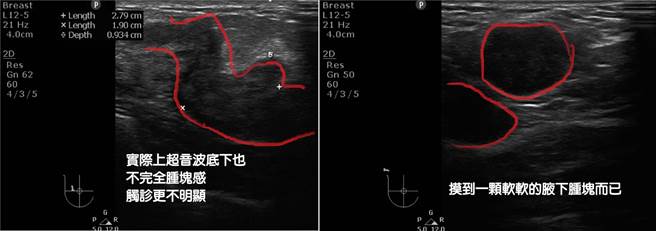

黄鸿铭日前于脸书粉专《杏妍诊所》指出,一名近40岁的女子上月施打莫德两周后,摸到右边腋下有颗粒般的肿块,但并无任何不适及疼痛感,一开始不以为意,后来还是决定就医检查。黄鸿铭替她触诊右侧乳房外侧时,隐约摸到一块软软、有弹性的肿块,但女子却毫无感觉。

黄鸿铭表示,经超音波检查后发现,该肿块大约3公分,再加上女子主诉右腋下摸到肿块,令他惊觉有异,赶紧将两处的检体送至病理中心检查,结果为右乳异常处侵袭癌,以及右腋下淋巴结淋巴转移,确诊乳癌